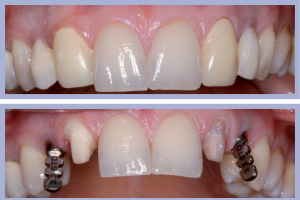

- Figg. 28a, b – Confronto tra inizio e fine trattamento

La valutazione clinica al momento della consegna dei manufatti e clinico-radiologica a 3 mesi dalla consegna manifestava una completa integrazione tissutale con eccellente recupero estetico e funzionale (Figg. 29-30).

I successivi passaggi portavano all’allestimento dei manufatti definitivi in zirconia-ceramica. In particolare venivano allestite tramite procedura CAD-CAM delle cappette in zirconia da incollare sui monconi per ottenerne una individualizzazione estetica; sempre con procedura CAD-CAM si ottenevano le strutture in zirconia successivamente ceramizzate per ottenere i manufatti definitivi (Figg. 23-25).

La consegna dei manufatti a supporto implantare veniva effettuata previa cementazione extra-orale degli stessi (Figg. 26-28).